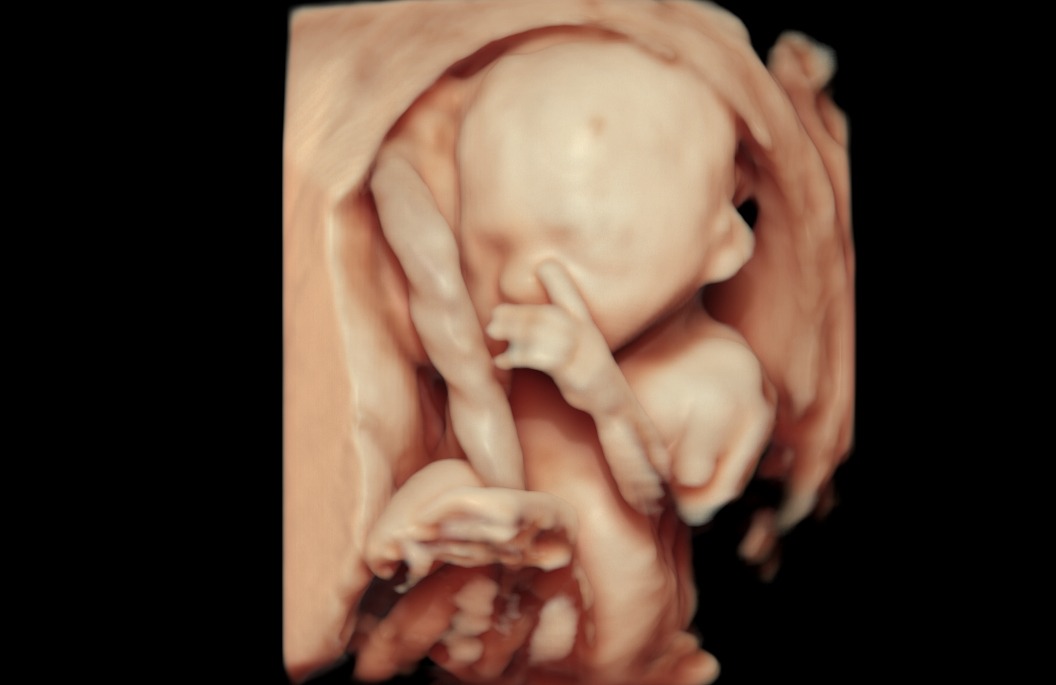

Naše klinika prenatální péče a genetiky nově disponuje nejvýkonnějším ultrazvukovým přístrojem na trhu –Voluson™ Expert 22 od GE Healthcare. Špičkový systém přináší zcela nový standard v oblasti prenatální diagnostiky.

„VolusonTM Expert 22 je přístrojem, který disponuje nejmodernějšími technologiemi pro zobrazování plodu ultrazvukem. Vysoká kvalita obrazu zaručuje mimořádně detailní a přesné zobrazení jednotlivých struktur plodu včetně jeho cévního zásobení. Tyto parametry nejen že zvyšují přesnost naší diagnostiky, ale hlavně posouvají naše možnosti záchytu vrozených vad do časnějších fází těhotenství. Kvalitní 3D/4D technologie zaručuje precizní posouzení prostorových vztahů. Bez její dostupnosti si dnes například nedokážeme představit cílené vyšetření mozku plodu a významně nám dokáže pomoci i v upřesnění celé řady dalších abnormálních nálezů. Takovéto přístrojové vybavení vnímáme jako nepodkročitelnou podmínku pro poskytování prenatální diagnostiky a té nejvyšší možné úrovni, “ prof. MUDr. Ivana Kacerovská Musilová, Ph.D. Odborný garant a gynekolog